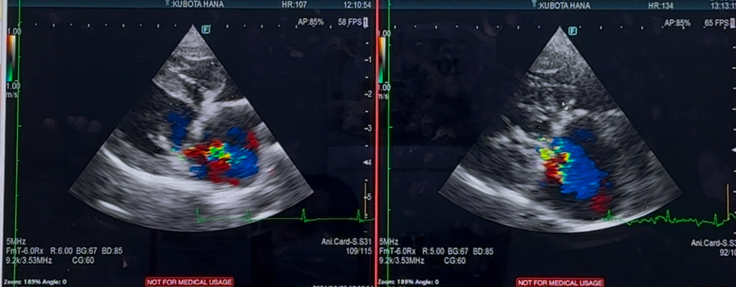

昨日は、華の心臓手術後13ヶ月半検診でした

心臓の方は

逆流が残っている所は

変わらず残っているまま…

心臓の大きさも、良くも悪くも

変わりなく…

術直後から「もう少し、ちぃさくなって欲しかったのですが…」と言われており…

標準値よりは、大きいままです…

右心の三尖弁の逆流や

肺高血圧症も、悪化はなく

中等度…